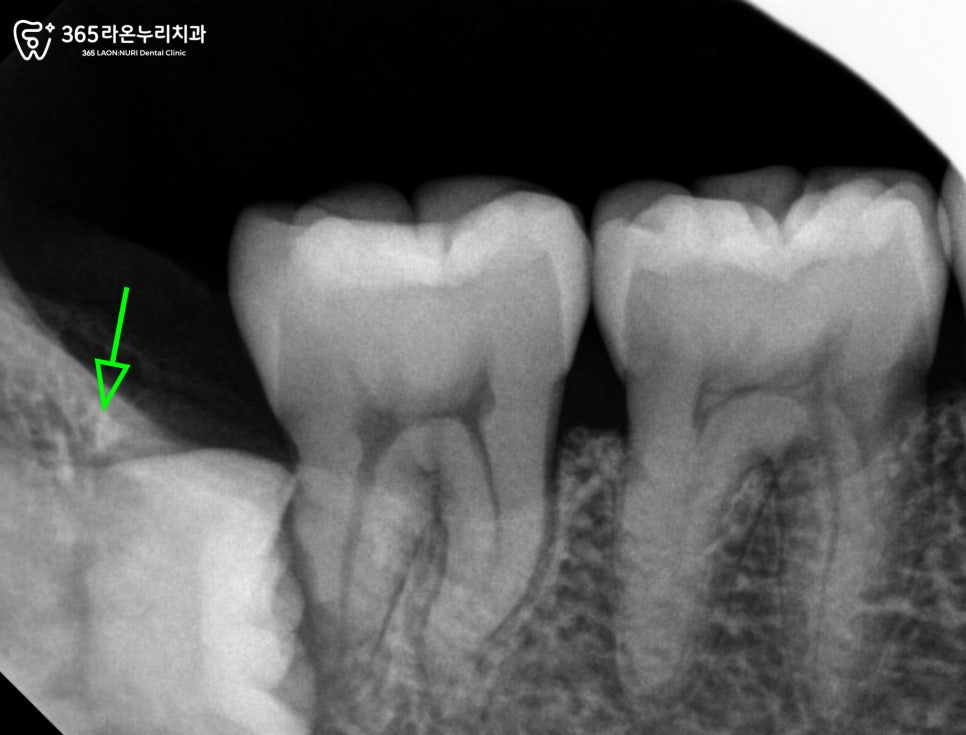

지금으로써는 오른쪽 아래턱에

누운 사랑니가 관찰되고 있었습니다.

이렇게 사랑니가 누워서

자라고 있는 경우 인접한

어금니를 지속적으로 밀게 되면서

염증을 유발하는 원인이 될 수 있습니다.

그렇기 때문에 오산 세교 치과 에서는

인접치에 영향을 줄 수 있는 사랑니를

지속적으로 관찰하며 상태를 점검하기로

했습니다.